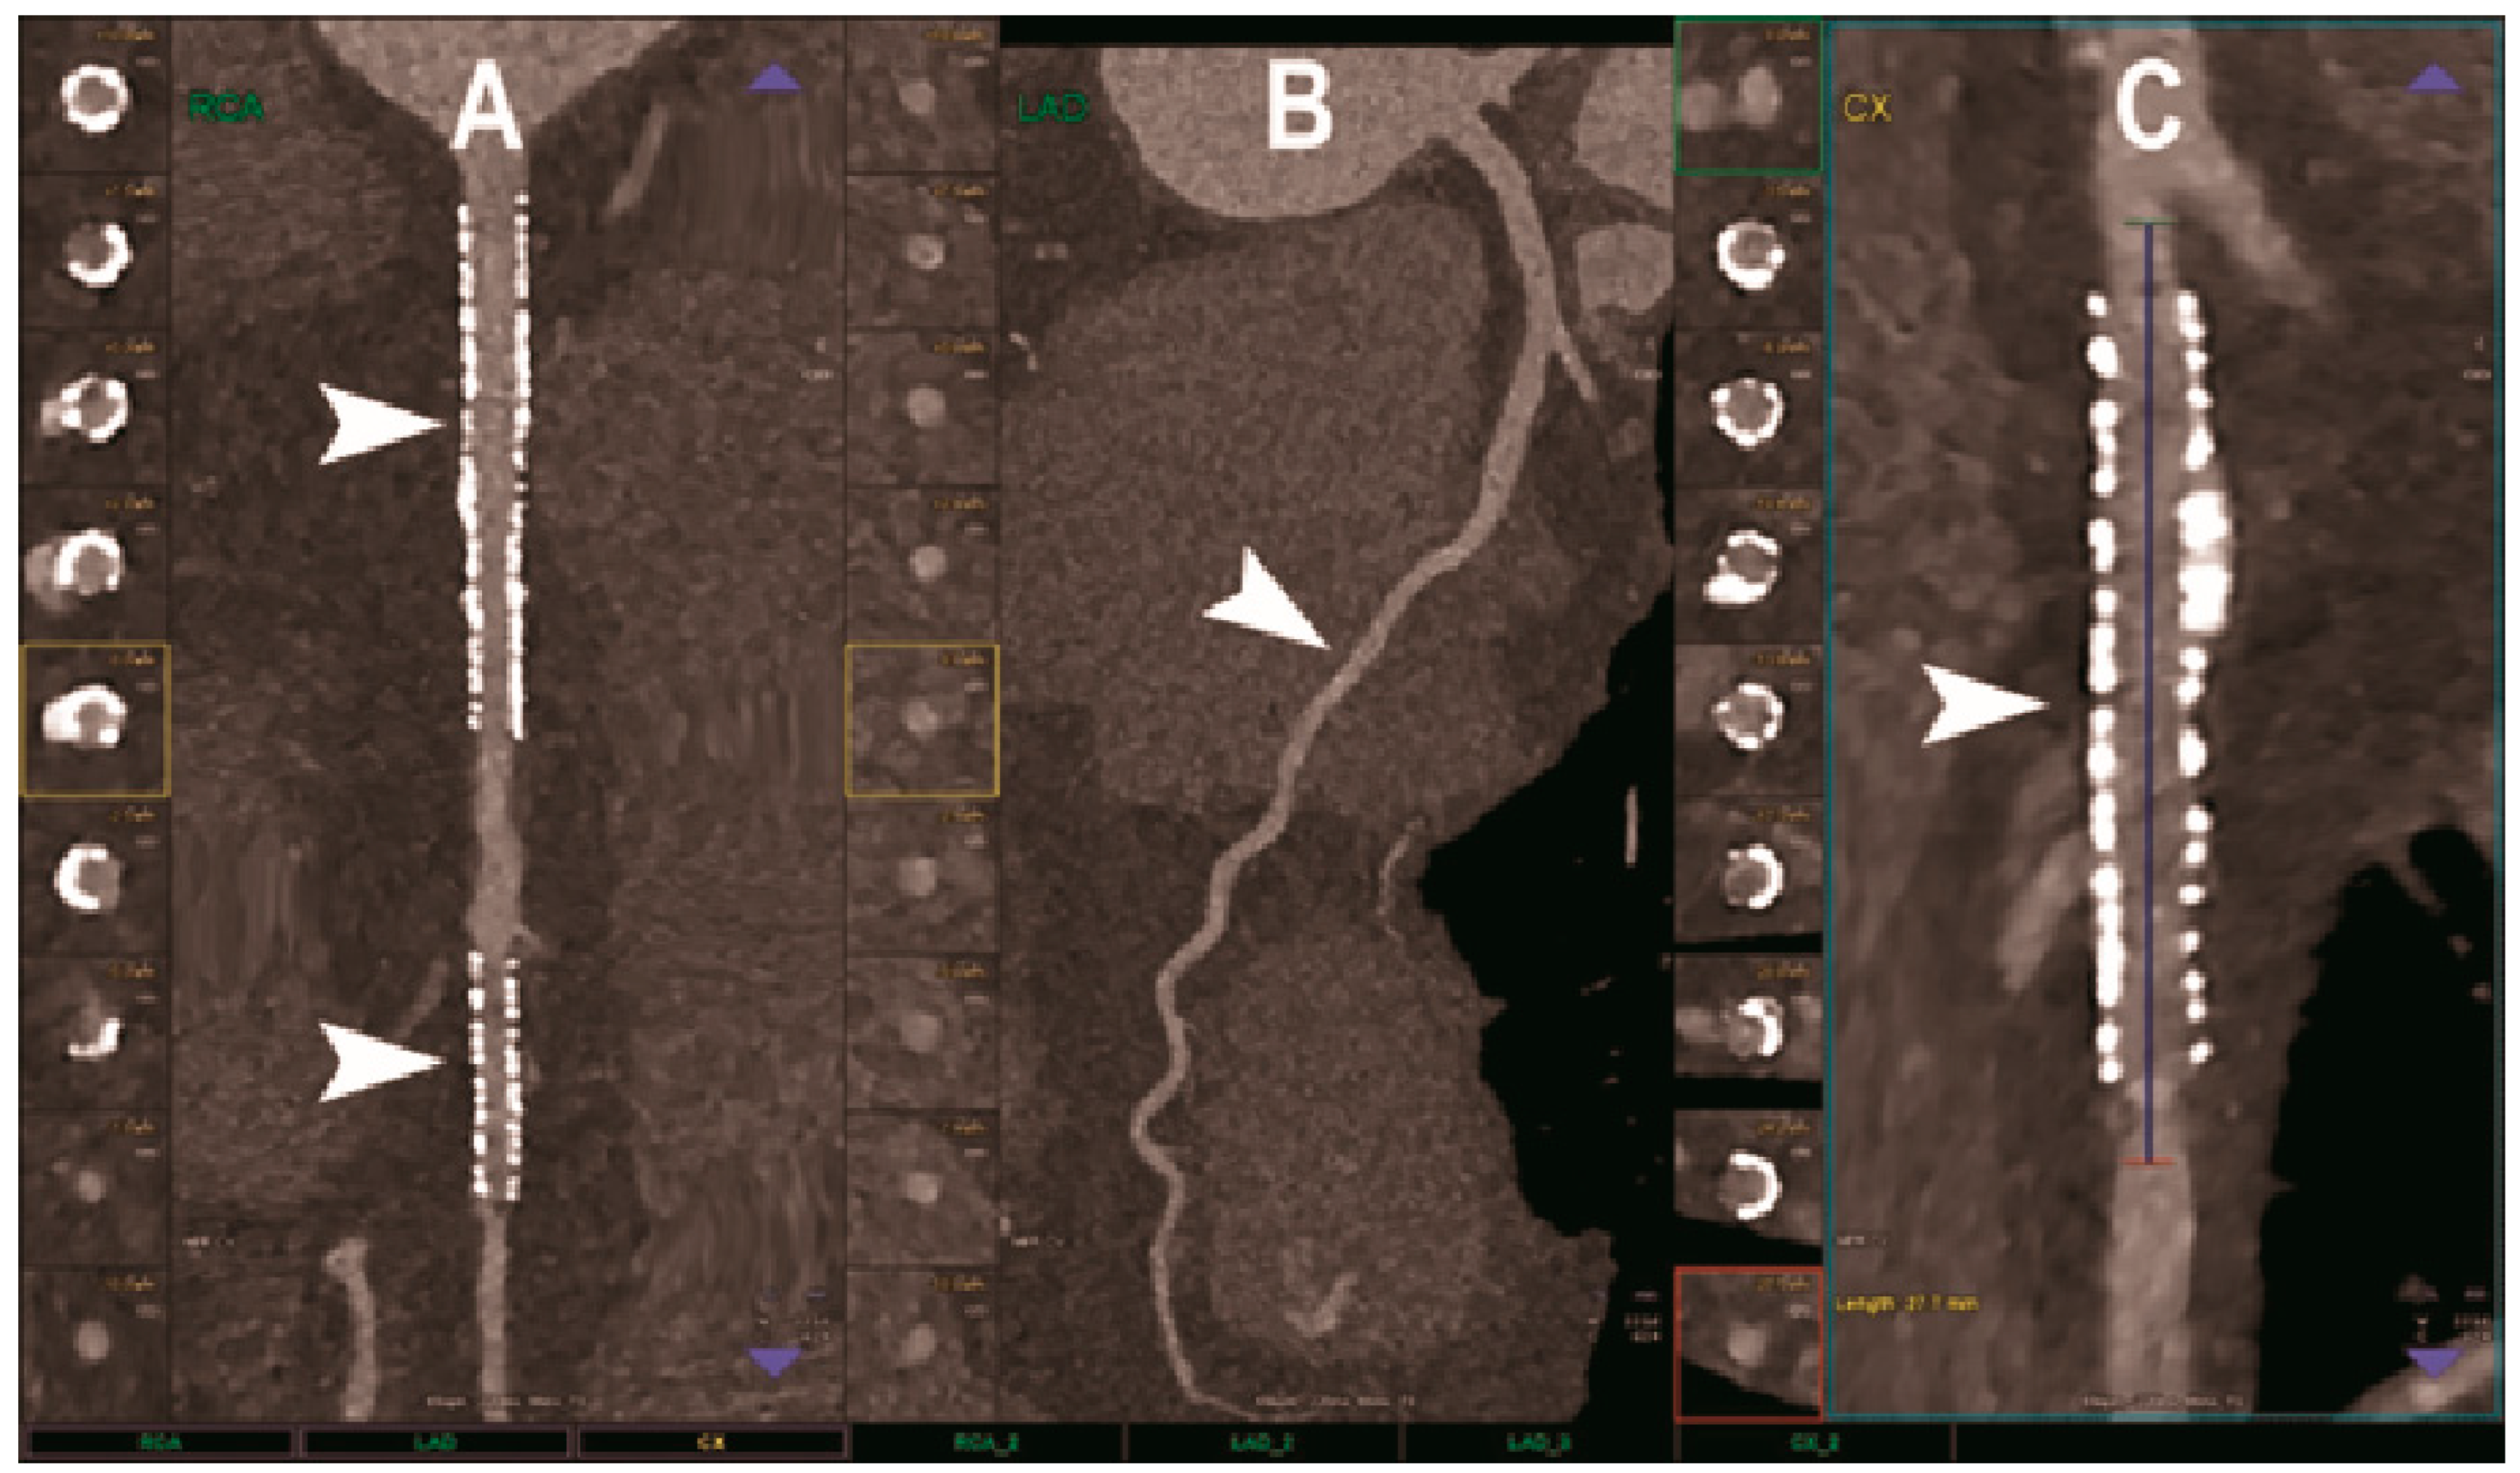

- Si-Mohamed, S.A.; Boccalini, S.; Lacombe, H.; Diaw, A.; Varasteh, M.; Rodesch, P.-A.; Dessouky, R.; Villien, M.; Tatard-Leitman, V.; Bochaton, T.; et al. Coronary CT Angiography with Photon-counting CT: First-In-Human Results. Radiology 2022, 303, 303–313. [Google Scholar] [CrossRef]

- Soschynski, M.; Hagen, F.; Baumann, S.; Hagar, M.T.; Weiss, J.; Krauss, T.; Schlett, C.L.; von zur Mühlen, C.; Bamberg, F.; Nikolaou, K.; et al. High Temporal Resolution Dual-Source Photon-Counting CT for Coronary Artery Disease: Initial Multicenter Clinical Experience. J. Clin. Med. 2022, 11, 6003. [Google Scholar] [CrossRef]